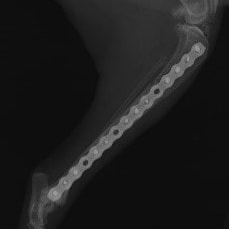

症例3:キルシュナーワイヤーのピンニングによる整復

ペルシャ猫 11ヶ月齢 雄

他院にて左大腿骨遠位の成長板骨折(salter-harrisⅠ型)が認められており、治療相談を目的として来院。当院にて、キルシュナーワイヤーを用いたピンニングにより骨折部位の整復を行いました。術後の経過は良好で、現在も経過観察中です。

術前レントゲン

術後レントゲン

機器

Arthrex社のターゲティングデバイスを用いてピンニングの位置を調整することで、確実な固定を行っています。当院ではこの手術器具以外にも、人の手術にも使用される様々な器具を導入し、手術精度を高め、また医療メーカーと新しい器具の開発、試作にも取り組んでおります。